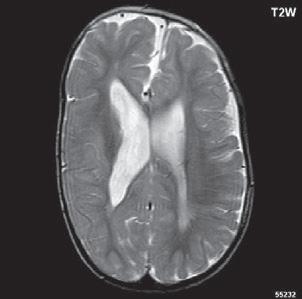

Obr. I.1.2a Paralelní postavení postranních komor, kolpocefalie, ageneze corpus callosum

Obr. I.1.2b Ageneze corpus callosum

Při agenezi corpus callosum CT i MR zobrazí paralelní průběh postranních mozkových komor (oproti fyziologickému

konvergentnímu průběhu) a jejich oddálení, časté rozšíření okcipitálních rohů – colpocefalie, někdy středočárový lipom, cystu. Koronální řezy ukážou rozšíření frontálních rohů postranních komor, III. komora je situována vysoko mezi postranní komory, tvoří jakoby trojzubec, který někteří autoři přirovnávají k přilbě Vikinga. Není patrné septum pellucidum. Častá je přítomnost středočárového lipomu nebo cysty.

Na vnitřní straně postranních komor pozorujeme v T2W obrazu poněkud tmavší strukturu než okolní myelinizovaná vlákna (naopak v T1W obrazu zvýšený signál), Probstovy provazce, axony, které za fyziologických okolností přecházejí přes corpus callosum do kontralaterální hemisféry.

Sagitální řezy nám přinášejí nejvíce informací o corpus callosum. Pozorujeme radiální průběh mozkových sulků ke stropu III. komory na vnitřní straně mozkových hemisfér a naopak nezobrazíme gyrus cinguli. Při parciální agenezi je postiženo především splenium.